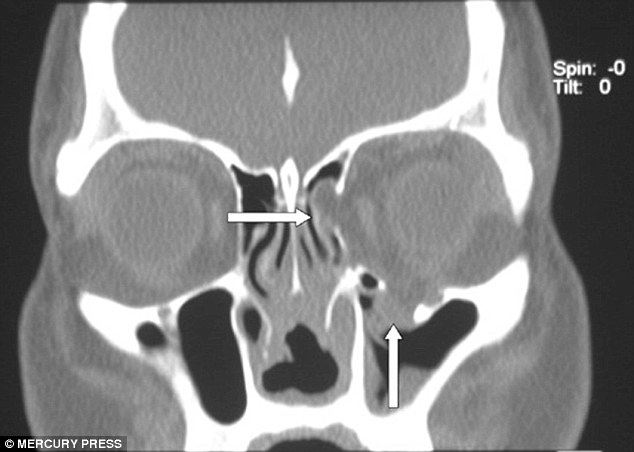

Khi cảm thấy những cơn mệt mỏi liên tục hành hạ, Lois Temel, 41 tuổi, đến từ Ryde, Úc đã đi khám bệnh, tuy nhiên bác sĩ không thể biết rõ nguyên nhân là gì. Cho đến khi họ chụp x-quang chiếc mũi cô, họ phát hiện ra cô gái đã bị nhiễm necrotising fasciitis - một loại bọ gây chết người có thể ăn mòn các mô mềm của cơ thể.

Cô cho biết thêm: "Tôi đã có khoảng một năm được nhiều bác sĩ thăm khám và không có hiện tượng gì. Chỉ đến khi, họ quyết định đặt một camera lên mũi của tôi thì họ phát hiện ra rằng bên trong hầu như trống rỗng. Tuy nhiên, bề ngoài thì hoàn toàn bình thường”.